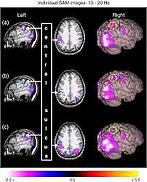

(Courtesy of distribution and temporal dynamics of brain, via sciencedirect.com)